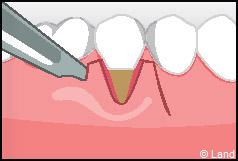

LES TECHNIQUES SANS APPORT DE GENCIVE :

Elles font appel à des lambeaux de gencive restante à proximité des récessions, qui sont déplacés et repositionnés sur la récession.